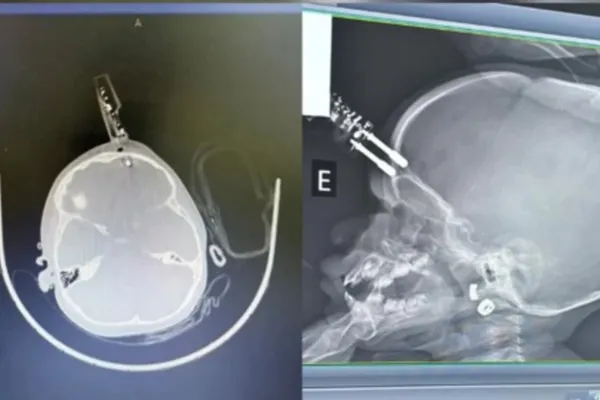

A bebê ficou com um carregador de celular preso na testa após cair de uma cama e precisou passar por uma cirurgia de emergência

O caso aconteceu na cidade de Divinópolis, na região oeste de Minas Gerais. O carregador estava em um colchão, colocado embaixo da cama onde a criança estava. Como ficou cravado na cabeça da bebê, o objeto precisou ser retirado via procedimento cirúrgico.

Ela foi inicialmente atendida na Unidade de Pronto Atendimento (UPA) de Divinópolis e, em seguida, transferida para o Hospital São João de Deus, onde passou por cirurgia imediata para retirada do objeto, correção da lesão e contenção de um pequeno sangramento.

Após o procedimento, a criança foi levada ao Centro de Terapia Intensiva (CTI), onde permaneceu por 36 horas. Ela passou por tomografia de controle e apresentou boa evolução clínica.